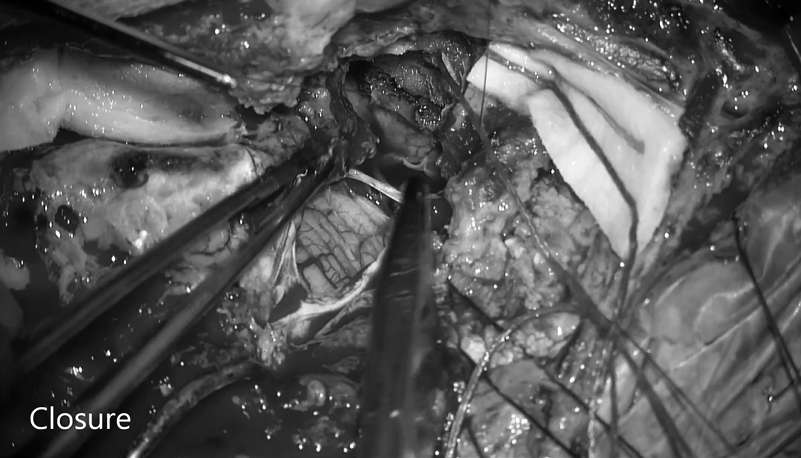

▼开始缝合、填充硬脑膜,完成硬脑膜缺损闭合,关颅